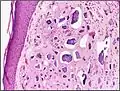

-

Calcinosis cutis in a dog with Cushing's syndrome -

Histopathology of calcinosis cutis in human tissue